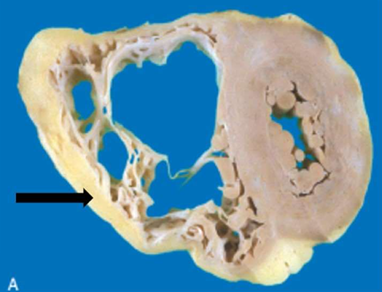

IHD: Myocardial infarction

Acute Myocardial Infarction

7-10 ds: the posterior wall of the left ventricle.

The yellow area (arrow) of necrosis is surrounded by a rim of dark, red granulation tissue.